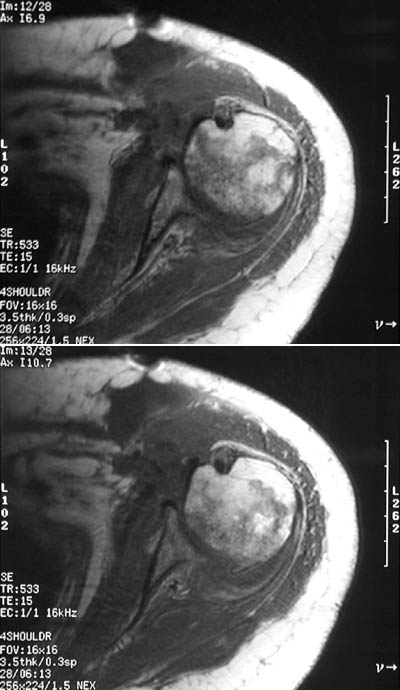

In these MRI scan views of the shoulder, there is irregularity in the proximal humerus due to the presence of avascular necrosis with chronic osteomyelitis.